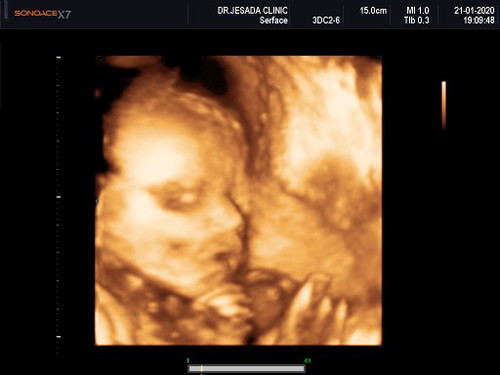

มาแชร์รูปน้องตอนซาวกันค่ะแม่ๆ